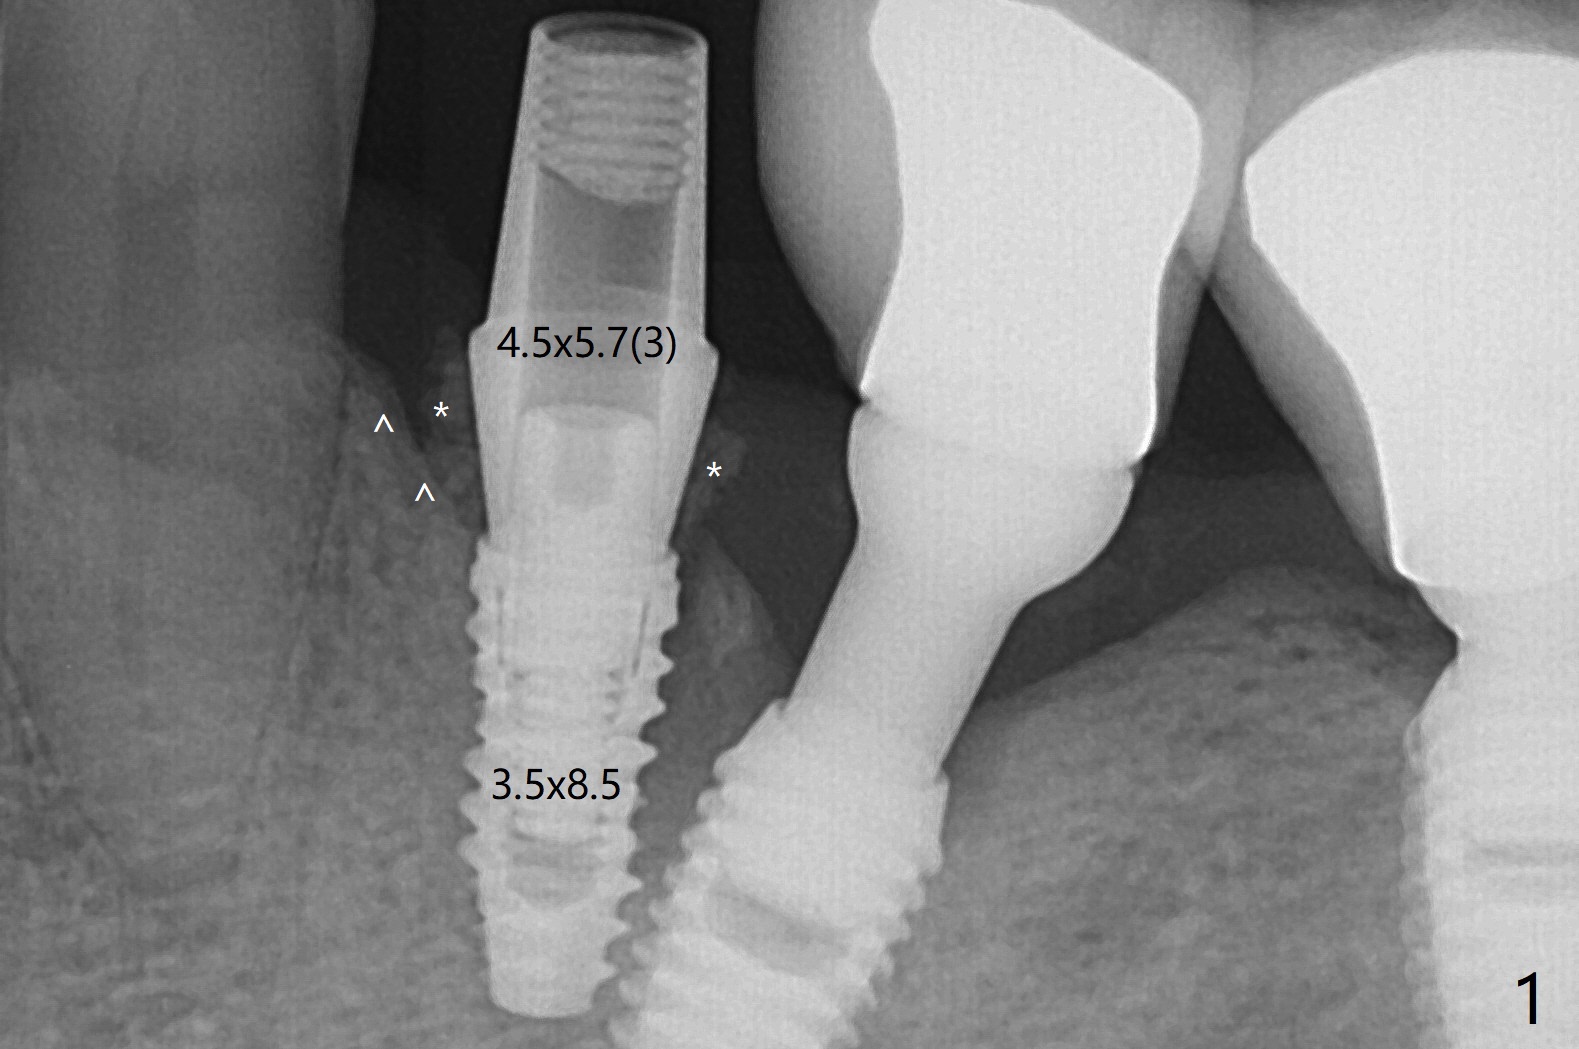

尽管使用导板,钻洞也不快,左下4植体仍旧偏移远中(图一)和颊侧(颊侧间隙比预计小),原因:斜面(图一:箭头),骨质硬,周围牙冠射线折射,导板就位前必须磨第二前磨牙近中面(今后遇到这些情景,选择徒手种植)。庆幸的是牙槽嵴水平两个植体还不是最接近(与根尖相比),粘性植骨(图一:*)但愿能缓解术后骨质吸收。制作临时牙冠后(图二:P),将PRF(图二:^;三:L(舌侧))插入牙冠和骨粉之间。术后六天软组织愈合正常(图四)。术后4个月远中牙槽嵴稍微下降(图五:*)。由于基台偏向远中,为了防止牙冠基台重新插入困难,基台不取出,先拧紧(20Ncm),牙冠口内粘固。